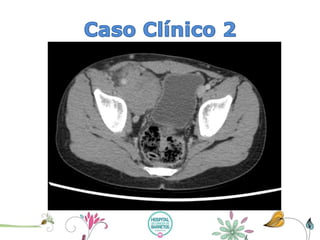

•WSS, masculino, Branco, 7 anos de idade, procedente de Monte Negro RO. Data 1º consulta 21/08/2013

•Há 18 meses iniciou com nódulo em região inguinal direita, de aumento progressivo que regrediu com cuidado local e antiinflamatório, sendo orientado retornar se necessário. Há 5 meses houve reaparecimento do nódulo de aproximadamente o tamanho de um limão pequeno, procurou auxilio médico que indicou a realização de biopsia, sendo realizado porém o resultado somente foi informado após 4 meses, quando o paciente já apresentava edema de membro inferior direito e aumento importante da massa em região inguinal. Neste momento foi informado a mãe que se tratava de um linfoma e foi encaminhada para o nosso serviço. Mãe negava febre, sudorese noturna e emagrecimento neste período.

•Exame físico de entrada: peso = 25 kg, estatura = 123 cm, BEG, corado hidratado ativo orientado no tempo e no espaço.

•Exame físico dirigido: Abdômen: FID massa que se estendia da crista ilíaca direita a região de sínfise púbica, em região inguinal direita conglomerado de linfonodosde +3 -4 cm de diâmetro, e edema compressivo de MID, pulsos preservados.

•HD Linfoma de Hodgkin Clássico, esclerose nodular.

Estadiamento

•CT de tórax: sem anormalidades

•CT de abdômen superior: sem anormalidades

•Biopsia óssea e Mielograma= sem anormalidades.

•Cintilografiaóssea = dentro da normalidade para faixa etária

•Pesquisa de corpo inteiro com Gálio –67: presença de atividade em processo tumoral em atividade nas projeções do mesogastroe gânglios inguinopélvicos à direita.

CT de abdômen inferior e pelve: Linfonodosinguinais à direita, medindo até 1,2 cm no menor eixo. Linfonodosilíacos externos à direita, o maior conglomerado envolvendo os vasos ilíacos, medindo até 4,3 cm no plano axial. A maior lesão desloca a bexiga para a esquerda.

•Linfoma Hodgkin, Clássico tipo celular esclerose nodular

•Estádio Clínico II A